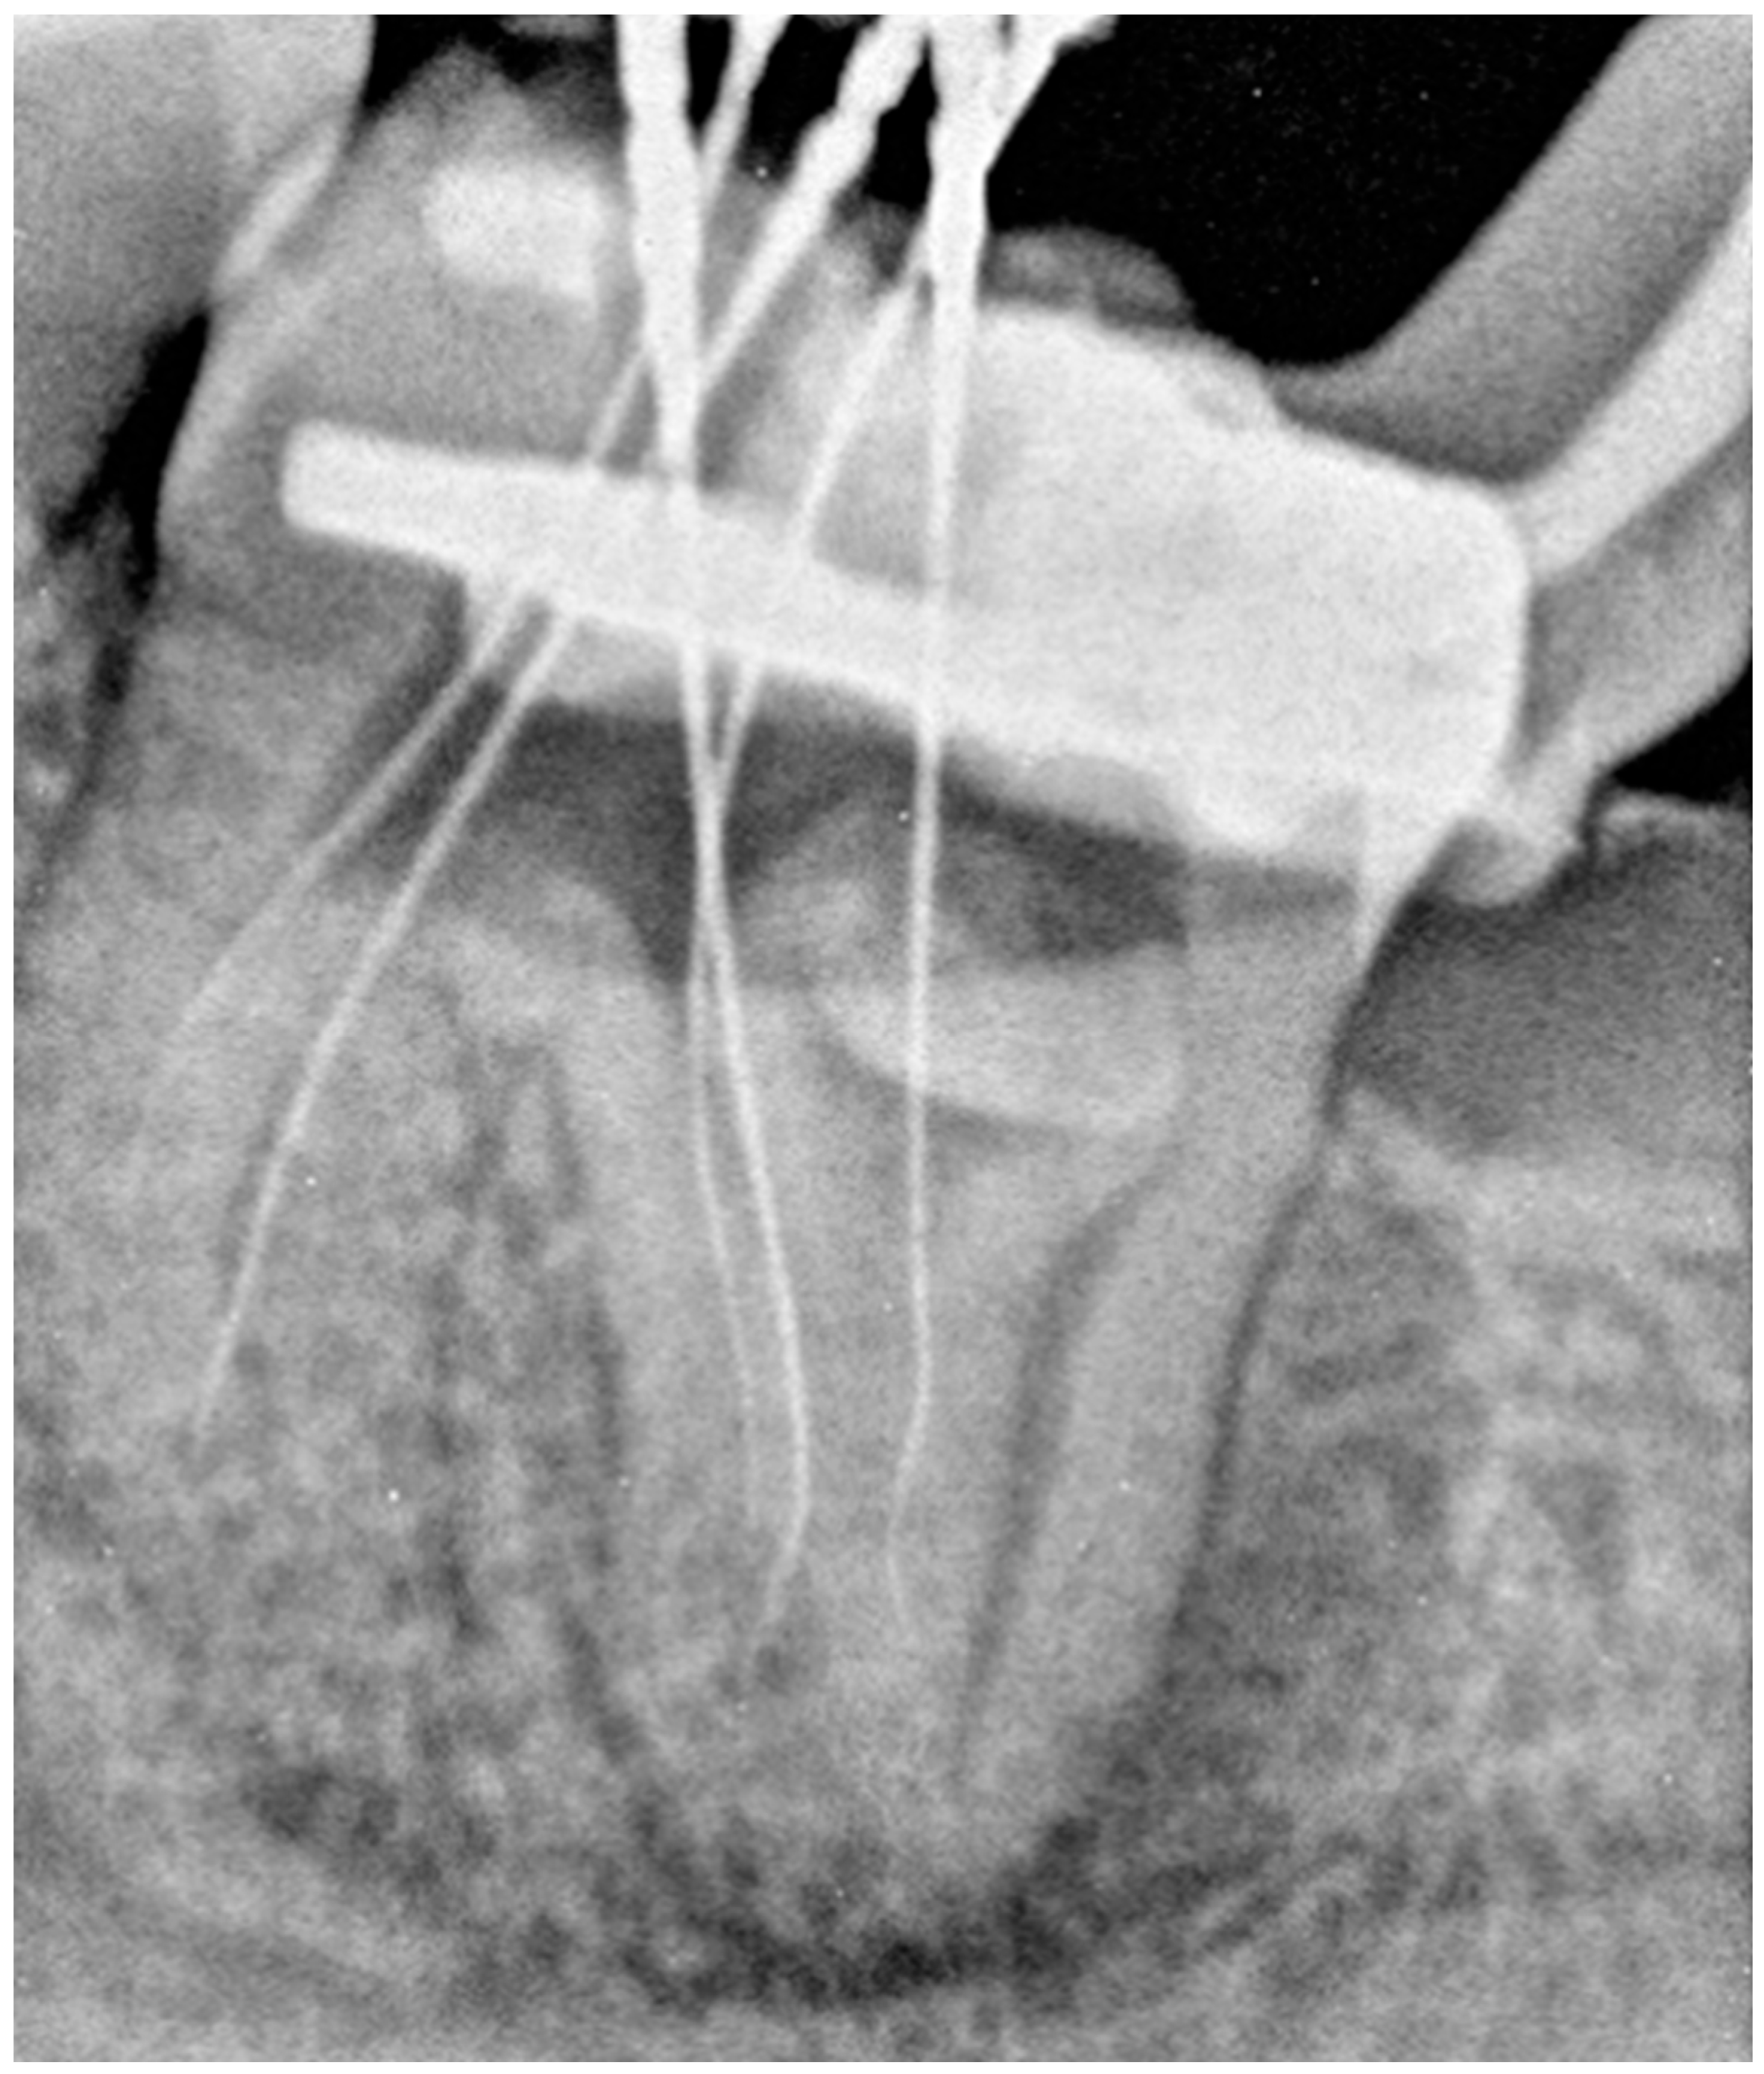

2.1. The First Visit

2.2. The Second Appointment